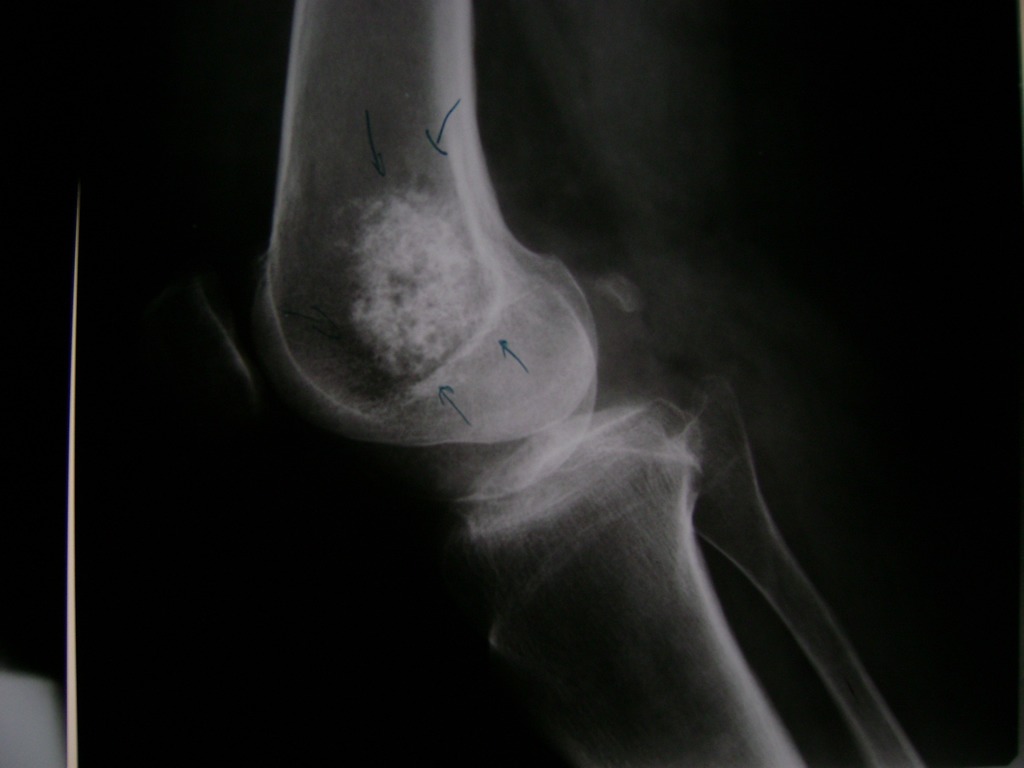

Húmero - Rodilla